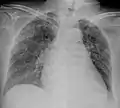

A case of miliary tuberculosis in an 82-year-old woman:

X-ray, 22 days after onset, showing extensive bilateral reticulo-nodular infiltrates